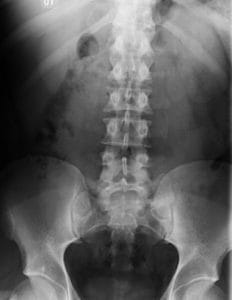

Una radiografía convencional de columna utiliza una pequeña cantidad de radiación ionizante para crear imágenes de las vértebras, los huesos que componen la columna. Los huesos, al ser densos, absorben más radiación y aparecen blancos en la imagen, mientras que los tejidos blandos como los músculos, nervios y discos intervertebrales aparecen en tonos de gris. Esta diferencia de contraste permite al médico visualizar la anatomía ósea con gran claridad.

Una de las grandes fortalezas de la radiología es su capacidad para evaluar la alineación espinal global. Se realizan tomas estándar de frente (anteroposterior) y de perfil (lateral) con el paciente de pie (en bipedestación). Esto revela cómo se comporta la columna bajo la fuerza de la gravedad.

El estudio permite al médico analizar si la columna mantiene su línea vertical recta desde arriba hacia abajo (alineación coronal) o si existen curvaturas laterales patológicas como la escoliosis. En la visión de perfil, se controlan las curvaturas naturales: la lordosis cervical y lumbar (concavidad posterior) y la cifosis dorsal y sacra (concavidad anterior). El equilibrio entre estas curvas es esencial para una postura erguida y sin esfuerzo.